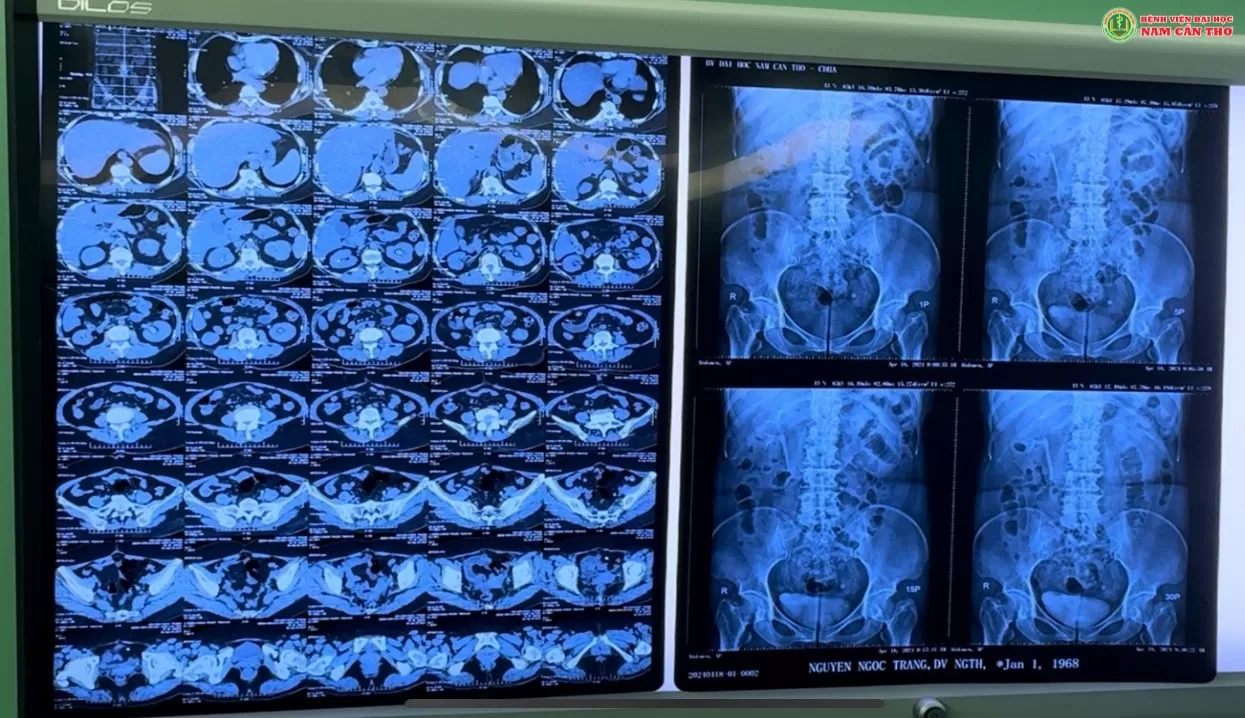

Vừa qua, bệnh nhân Nguyễn Ngọc T., 56 tuổi, tại Thành phố Cần Thơ cho biết thấy thường xuyên đau âm ỉ vùng hông lưng trái nên đến thăm khám tại Bệnh viện Đại học Nam Cần Thơ. Sau khi thăm khám và thực hiện chụp cắt lớp vi tính, các bác sĩ chẩn đoán bệnh nhân bị sỏi niệu quản trái, thận trái ứ nước độ I do sỏi niệu quản kẹt đoạn nội thành bàng quang, sỏi thận 2 bên.

Ảnh chụp cắt lớp vi tính của bệnh nhân T